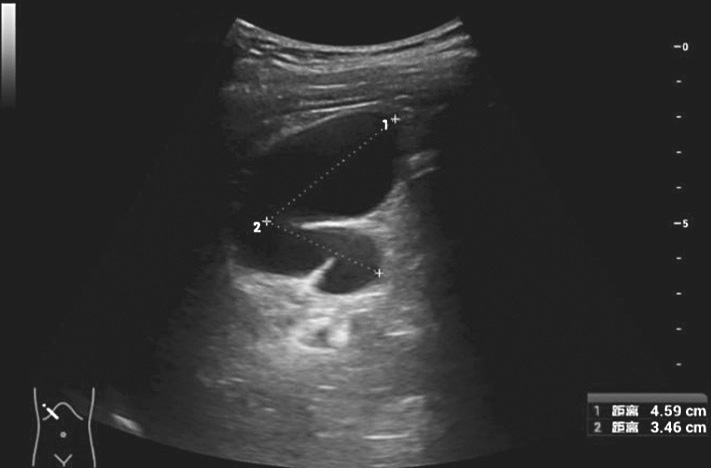

①胆囊长径:测胆囊颈部至胆囊底部内腔最大长径,如胆囊明显折叠,则分别测颈部至折叠、折叠至底部两段径线并相加(图2-1-5)。②胆囊横径:与胆囊长径垂直的径线。

图2-1-5 胆囊长径测量

当胆囊出现褶皱时,测量两个径线后相加